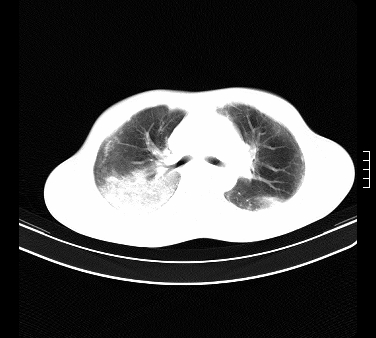

患者,男,17岁,系我院急诊科收治的一例百草枯中毒患者,做ct检查时,距离服药的时间为3天。上传与大家分享

补充:百草枯进入人体内主要分部于肺和骨骼,肺部损伤24小时内出现水肿,2-3天内出现急性呼吸窘迫综合征,1-2周内出现肺纤维化。(引自陈灏珠,实用内科学12版)

不错,挺好。符合呼吸窘迫综合征